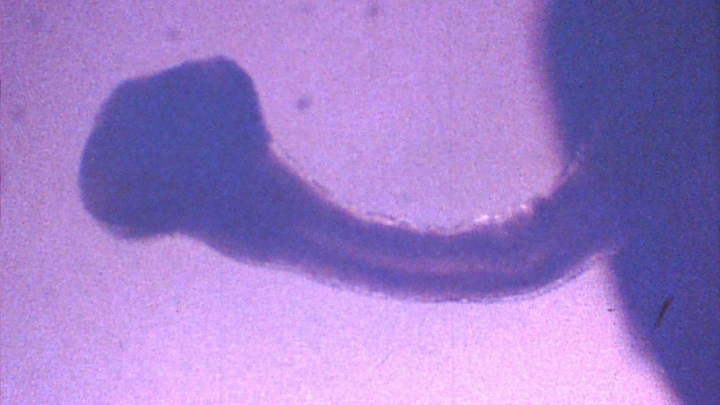

Taenia solium, or the pork tapeworm, is one of the world's most dangerous parasites. It can lodge in the brain tissue where it can cause seizures and even death. It has now been successfully been raised outside the body. This is hugely useful to researchers, who can now experiment with how best to kill it.